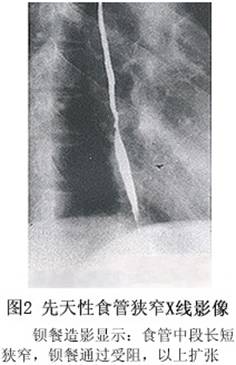

1.食管钡餐造影 根据钡餐造影的影像特点,食管狭窄可分两型.

10种食管钡餐常见疾病图解